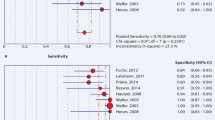

ROC analysis

ROC analysis of uptake intensity with 3 categories and calcification (Fig. 1) revealed FDG uptake intensity to be the only discriminating criterion, with an AUC of 0.90 (95% CI 0.87–0.92). Calcification showed no relevant discrimination ability by itself, with an AUC of 0.62 (95% CI 0.58–0.66). However, as absence of calcification only occurred in GCA, calcification was combined with uptake intensity into a 2-component, 6-tiered scoring system to assess if calcification would add to the discriminative ability of uptake intensity. For this purpose, calcification was simplified to ‘present’ or ‘absent’. Combining the two criteria resulted in a 6-tiered categorization ranging from < Liver uptake + calcification, representing maximum likelihood of atherosclerosis, to > Liver uptake + no calcification, representing definite presence of vasculitis (Table 4, upper section).

Whilst the 6-tiered scoring method had similar discriminatory ability (AUC 0.91; 95% CI 0.88–0.93; Fig. 2) to uptake intensity alone, it did allow for more efficient sorting of cases. For example, the highest score in the 6-component method (uptake > liver and no calcifications) denoted certain vasculitis, whilst based on high vascular uptake alone, several atherosclerosis cases would still have been mistaken for vasculitis (Table 4, top section). Using 6 tiers did however create several small groups in some of the components. To see if these could be eliminated without affecting the AUC, the combined scoring criteria condensed into 4 tiers by merging uptake < liver and uptake = liver was also analysed (Table 4, lower section). The ROC analysis of the 4-component combined method showed an AUC that was comparable to the 6-tier method (0.8; 95%CI 0.87–0.92; Fig. 2).

The presence of patients with vascular prostheses may have influenced the results. To evaluate this, 8 image sets with vascular prostheses were removed from the dataset. The censure of cases with prostheses resulted in an increase in AUC to 0.93 (95%CI 0.91–0.95; Fig. 3) for the 6-tiered method. This increase, albeit modest, suggested that it may be beneficial to eliminate arteries containing vascular prostheses from scoring. With the cut-off value set at tier 4, over half of patients risking misclassification based on uptake > liver were eliminated by removing prostheses, from 47 to 21 patients (Table 5). Table 6 summarizes the discriminatory value of all assessed scoring methods.